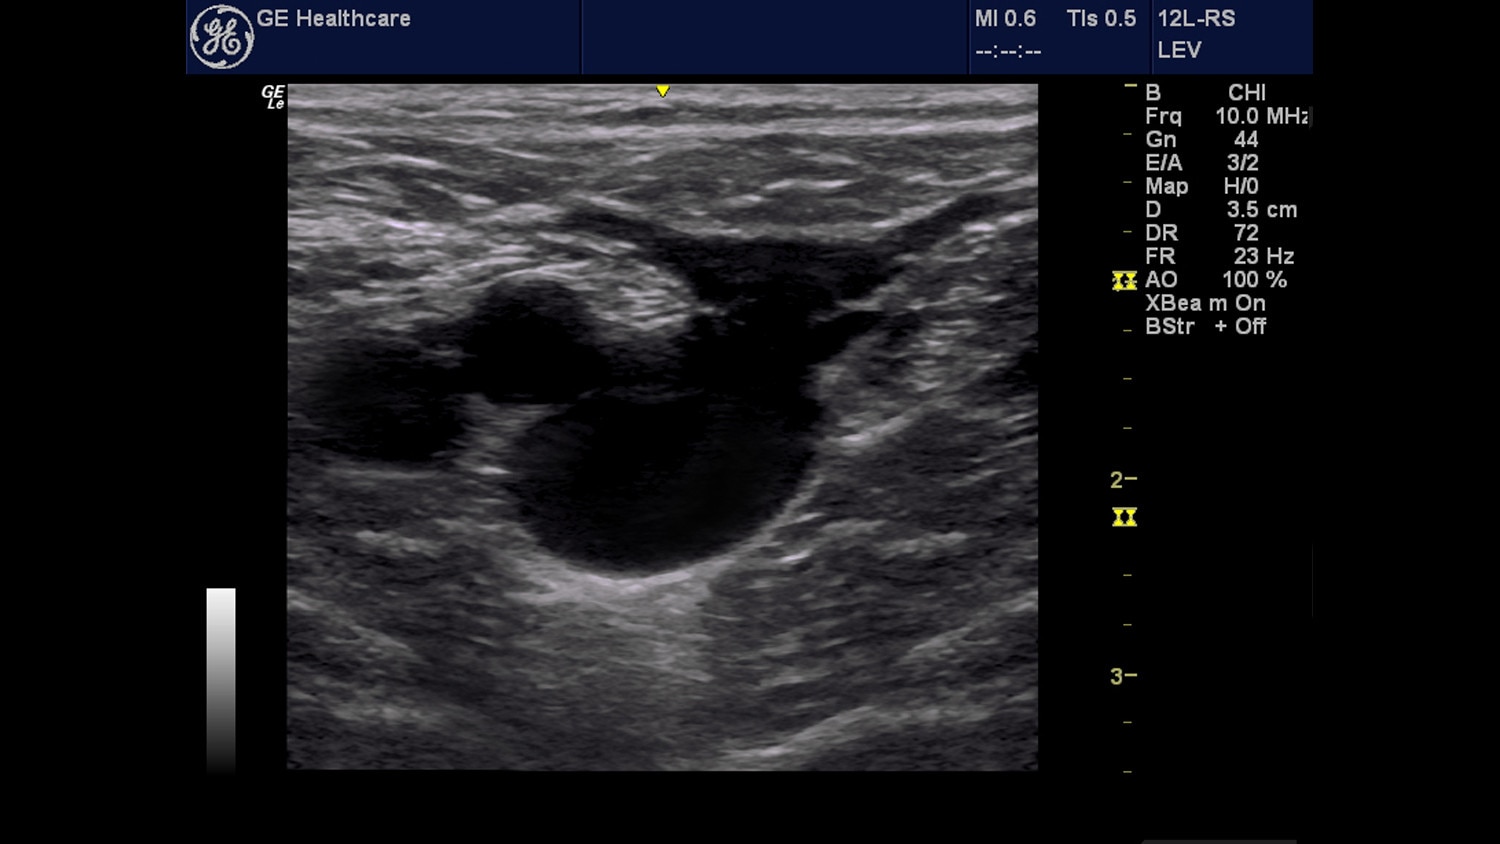

Venous

Overview